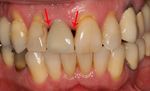

Black triangles

Black triangles caused by bone loss between implants and natural teeth